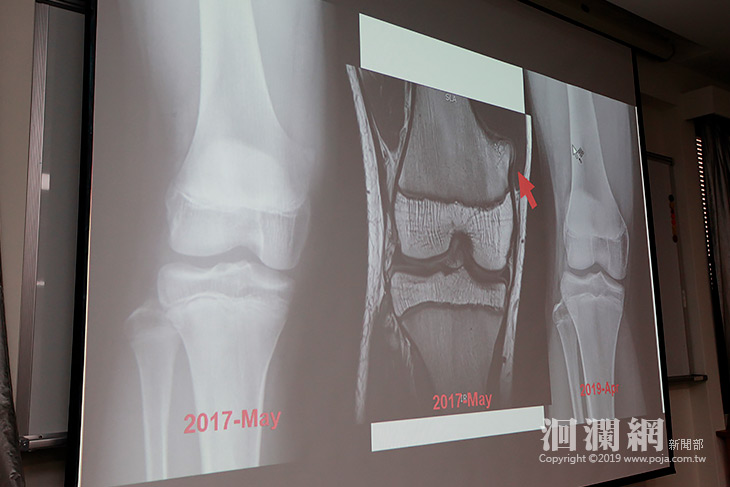

16歲青少年2年前因膝蓋疼痛就醫,診斷為骨軟骨瘤作祟,由於未影響生活,醫師建議先觀察再決定後續是否開刀切除,近日青少年因打籃球引起雙側腳踝疼痛回診就醫,經醫師安排X光檢查後,意外發現原本如乒乓球大小的骨軟骨瘤竟然消失不見。門諾醫院骨科醫師蔡傳恩表示,骨軟骨瘤是一種常見的腫瘤,大多好發在年輕人身上,大部分的骨軟骨瘤會與患者和平共處,但自動消失不見確實罕見。

蔡傳恩說,「骨軟骨瘤」消失在國際上是零星案例,50年間也僅有23篇報告提到自行縮小甚至消失。其消失的原因在假設理論上,有可能是骨骼成熟的過程中,腫瘤融合到生長中的骨骼內部,或是腫瘤遭受外傷甚至骨折,影響腫瘤的血液供應,而推斷少年骨軟骨瘤消失的原因有可能是因為青少年還在長高,骨軟骨瘤被拉平。